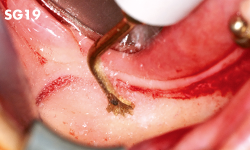

Avulsion of wisdom teeth and impacted teeth

Sinus graft

Sinus membrane

Sinus graft